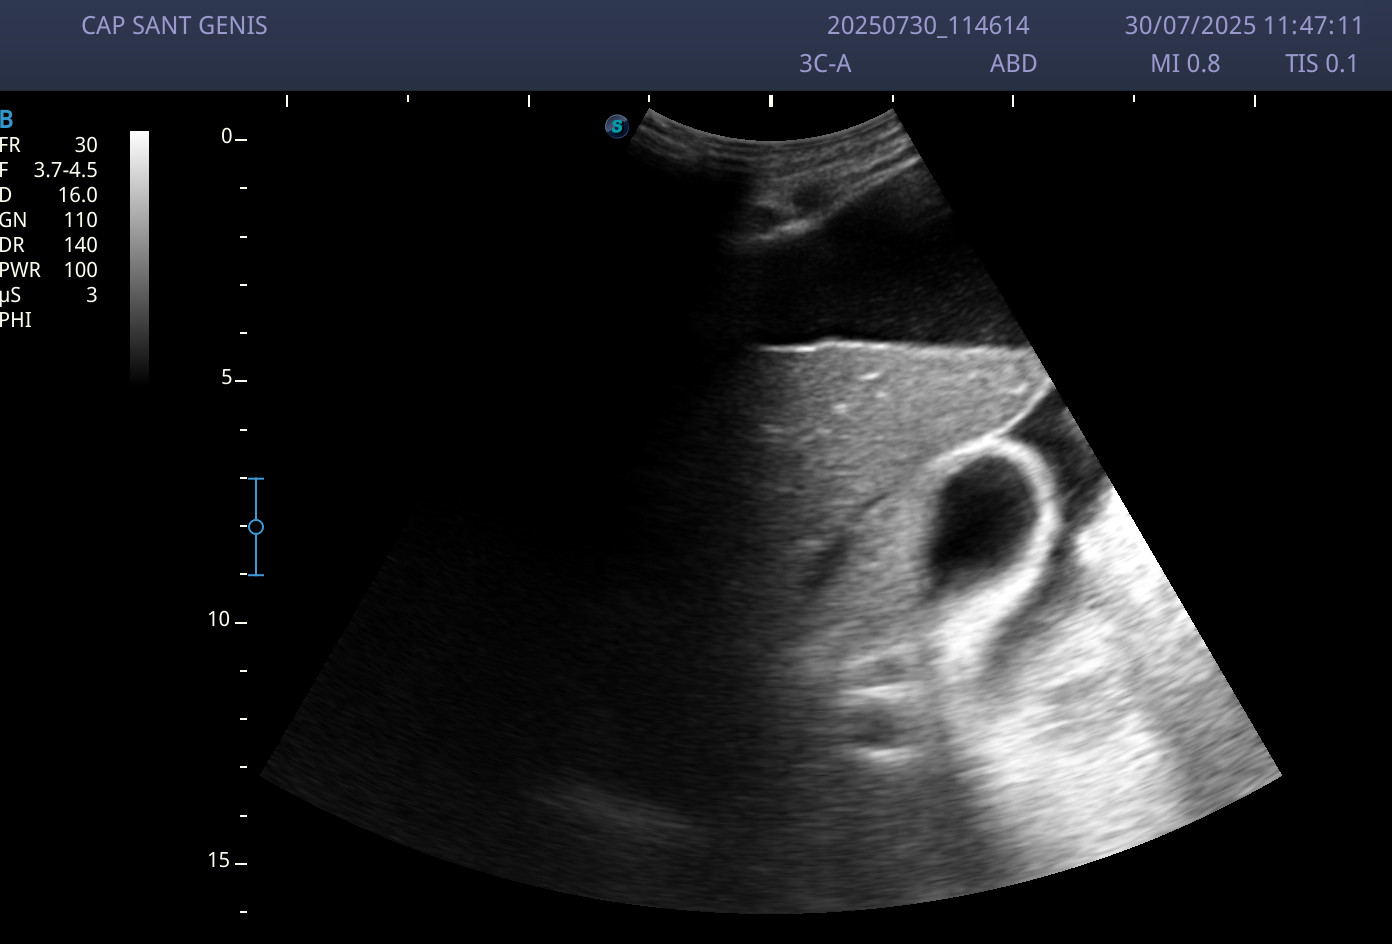

Ecografía abdominal: abundante ascitis perivisceral, y sobre todo a nivel perihepático.

Ante la sospecha de ascitis secundaria a insuficiencia cardíaca congestiva se deriva al paciente a urgencias hospitalarias.

Ante los hallazgos ecográficos, y el resto de exploraciones complementarias ingresa con el diagnóstico de Insuficiencia cardíaca descompensada.